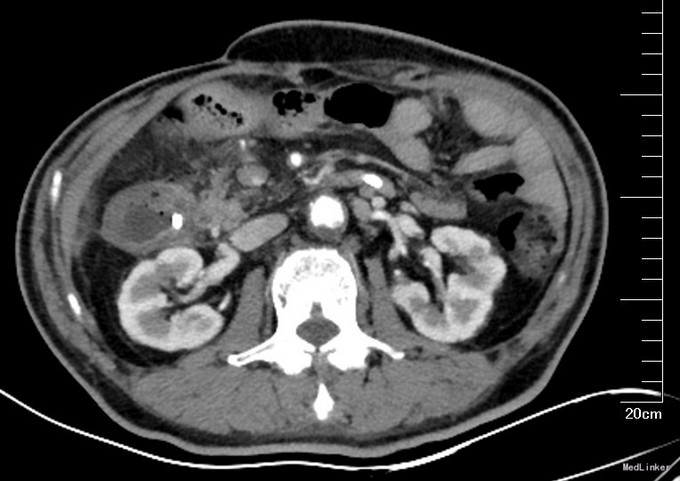

入院后,复查全腹增强CT(图3,图4):结节较前缩小。胃壁增厚。肠癌系列正常。行PET-CT:1、原右肾门水平十二指肠前方FDG高代谢软组织影区域本次扫描代谢未见显著增高,符合治疗后改变。2、右肺上叶多发磨玻璃影,FDG代谢略高,注意重度不典型增生,3、胃窦远端FDG代谢略升高,目前考虑炎症可能大,需密切结合镜下及病理;十二指肠管壁增厚伴周围多发渗出,炎性改变可能大。胃镜:窦前壁近幽门管可见一溃疡性病变,大小约1.5*2.0cm,表面白苔,周围粘膜充血水肿。幽门口变形,收缩舒张不良。十二指肠球部粘膜充血,球后黏膜光滑、色泽正常。此次病理:胃溃疡性病变,局部腺体轻度非典型增生,幽门螺杆菌阴性。上消化道造影(图5):胃窦部变形,胃壁略僵硬。 考虑患者胃窦部病变不能除外恶性。同时肺内病灶不能除外恶性。考虑为肿瘤的复发及远隔转移,手术治疗效果不佳,予以口服化疗药物治疗。空肠营养管建议终身携带,帮助增强营养,如患者不耐受,可以改为内镜下经胃造瘘空肠营养管(PEJ)。随访。